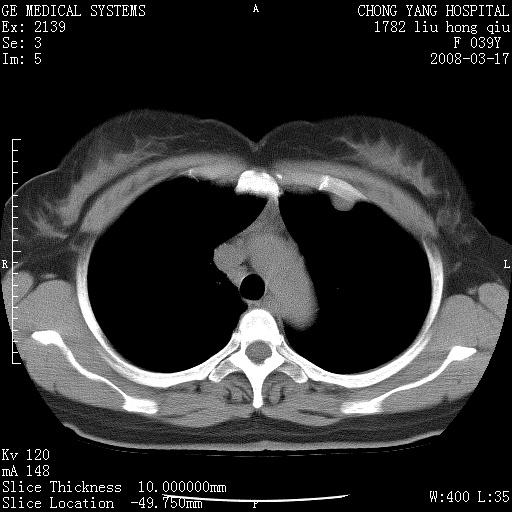

以下是引用yangxue121在2008-5-31 20:24:00的发言:[br]考虑多发胸膜间皮瘤[br]左侧少量胸腔积液[br]肝脏密度不均

以下是引用王仕学在2008-5-31 20:10:00的发言:[br]考虑胸膜间皮瘤。

以下是引用长城干红在2008-5-31 21:42:00的发言:[br]肝脏密度不均,建议增强扫描,胸膜下多发结节,考虑为胸膜来源的原发肿瘤或转移瘤。